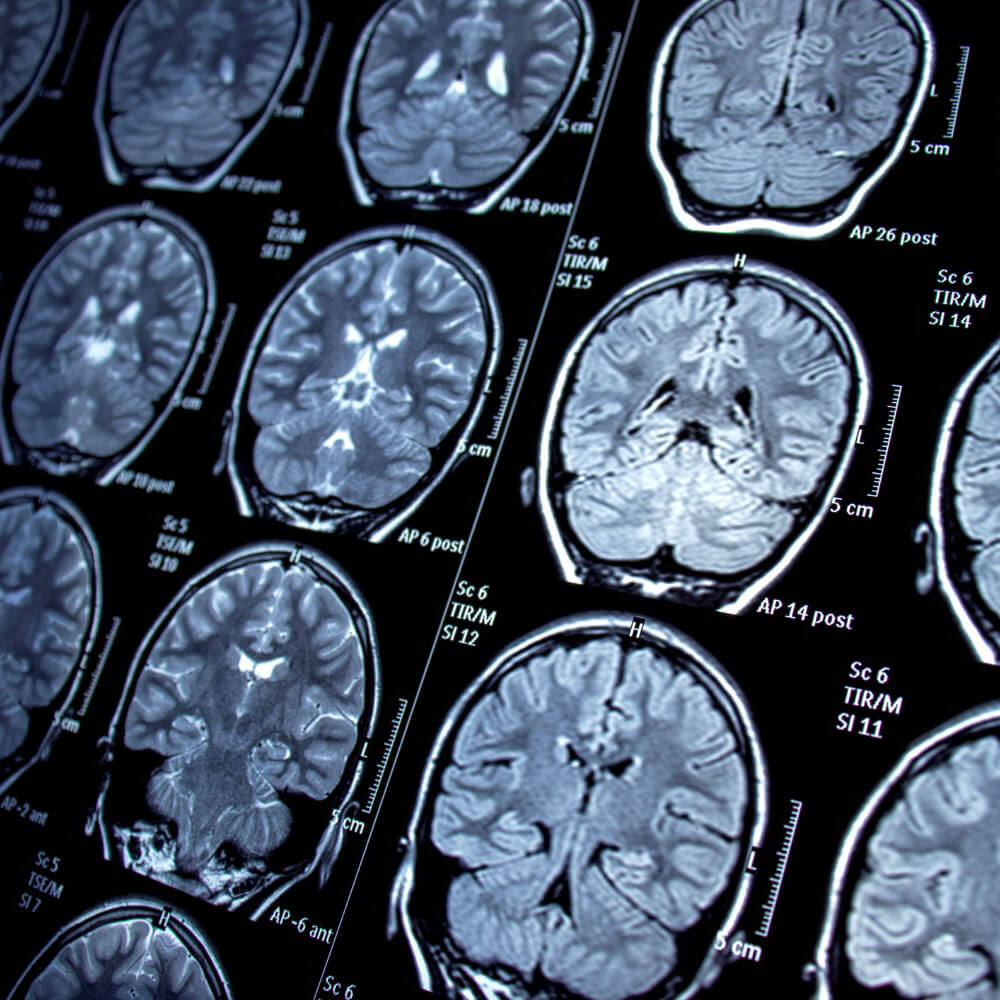

A Ressonância Magnética é um exame de imagem avançado que utiliza campos magnéticos e ondas de rádio para gerar imagens detalhadas dos órgãos e tecidos do corpo. Diferente de outros métodos de imagem, como o Raio-X e a Tomografia Computadorizada, a Ressonância Magnética não utiliza radiação ionizante, tornando-a uma opção segura e eficaz para uma variedade de diagnósticos.

Na Tomoson, utilizamos a Ressonância Magnética 3T de última geração. Esta tecnologia avançada proporciona imagens mais nítidas e de maior qualidade, permitindo diagnósticos mais precisos e detalhados. A alta resolução da Ressonância 3T é especialmente benéfica para identificar pequenas lesões e anomalias que podem não ser detectadas por outros métodos de imagem.

• Imagens de Alta Definição: A maior potência do campo magnético (3 Tesla) gera imagens com alta resolução, proporcionando detalhes excepcionais dos tecidos e órgãos.

• Maior Precisão Diagnóstica: A clareza das imagens facilita a detecção de pequenas alterações, contribuindo para diagnósticos mais precoces e tratamentos mais eficazes.